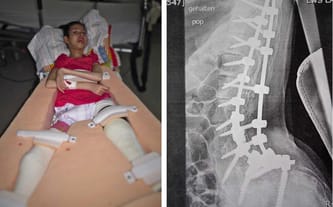

Niestety w 2015 roku wszystko ponownie legło w gruzach… Stan Basi bardzo się pogorszył – doszło do zwichnięcia stawu biodrowego. Z powodu ogromnego bólu przestała chodzić do szkoły i siedzieć. Od grudnia 2015 roku do kwietnia 2017 roku przeszła 7 operacji...

Niestety kilka miesięcy spędzone w łóżku bez rehabilitacji z ciągłym bólem doprowadziły do znacznej skoliozy. Ucisk na nerwy powodował ból i konieczna była kolejna operacja, tym razem kręgosłupa. (otwiera nową kartę) Dzięki Waszej pomocy udało się uzbierać niewyobrażalną kwotę, która pozwoliła na przeprowadzenie operacji! Jesteście wspaniali, dziękuję to za mało… Wciąż jednak potrzebna jest Wasza pomoc!